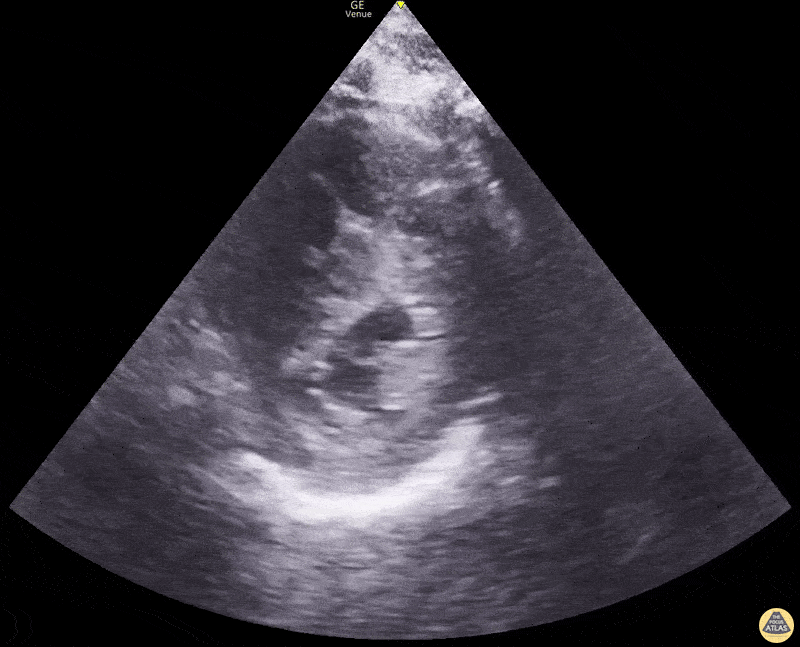

Right Ventricular Dysfunction - D Sign in Right Heart Strain

Parasternal short axis view with interventricular flattening showing a ‘D-sign’ consistent with right heart strain in this patient with an acute pulmonary embolism Dimitri Livshits DO, Ultrasound Fellow; Jane Belyavskaya MD, Ultrasound Fellow; Chris Hanuscin MD, Ultrasound Division Director (Kings County/SUNY Downstate)